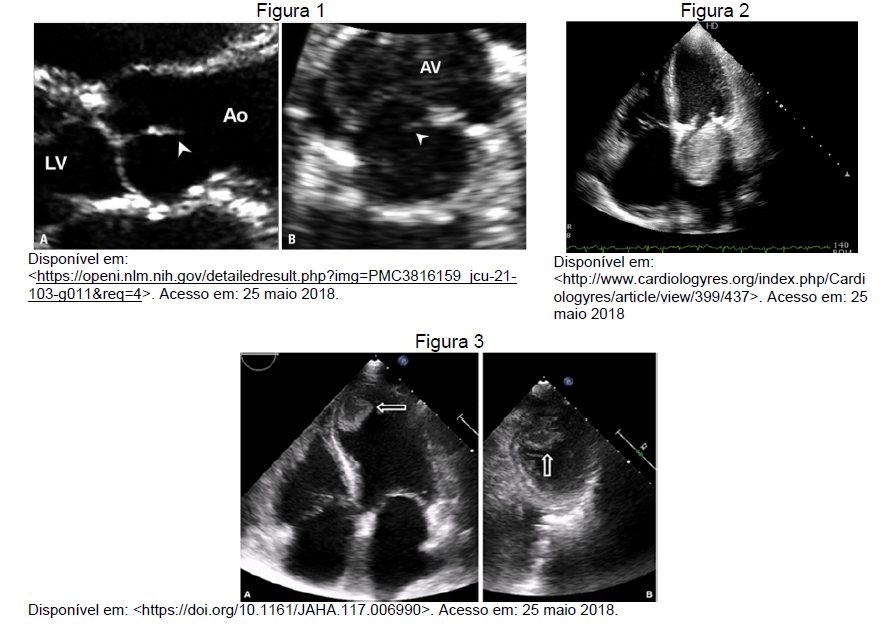

Observe as figuras 1, 2 e 3 para responder à questão 29.

Sobre os diagnósticos das massas em evidência nas figuras 1, 2 e 3, respectivamente, é correto afirmar que provavelmente são: